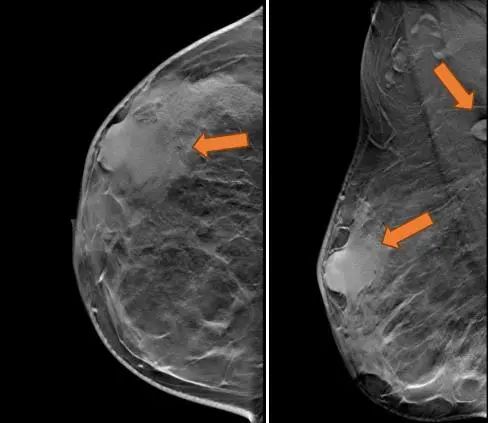

2021.7.7乳腺MRI:右乳外上象限肿物(BI-RADS-6)3.1cm×1.9cm×3.0cm,右腋窝见肿大淋巴结,M灶可能。

右乳外上象限见不规则肿块,呈长/稍长T2、等T1信号,DWI呈高信号,ADC图信号减低,ADC值约0.863,增强扫描明显强化,TIC呈Ⅲ型,大小约3.1×1.9×3.0cm,邻近皮肤增厚,皮下脂肪层模糊,另肿块外侧旁见小肿块影,增强明显强化,与外上象限肿块相连。右侧腋窝见肿大淋巴结。

图3. 乳腺MRI

(3 cycle 后)2021.9.22 复查乳腺MRI示:右乳肿块较前减小14mm×9mm×18mm。

图7. 乳腺MRI